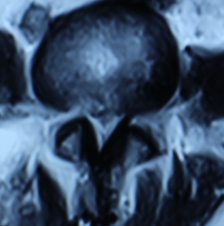

1.患者邹某,男,79岁,因“腰痛双下肢疼痛1年余,加重并间歇性跛行2月”于2014年3月26日入院。入院见患者腰痛病双下肢疼痛、麻木,间歇性跛行,行走约10余米,休息后略缓解。查:直腿抬高试验左40°(+),右55°(+),加强试验(+),腰背伸试验阳性。双侧膝腱未引出,跟腱反射减弱,双侧踇背伸肌力Ⅳ级。入院后诊断为腰椎管狭窄症。患者既往患糖尿病、高血压、冠心病病史。入院后完善检查,明确诊断,请相关科室会诊后认为手术风险极大。经科室讨论后行经皮椎间孔镜下髓核摘除并椎管扩大成形术,手术麻醉方式为局麻。于2014年3月29日行手术治疗,经椎间孔入路椎间孔镜下髓核摘除椎管扩大成形术。手术顺利,术中无出血,手术时间约40min。术中可与患者交流。术后患者即可感双下肢无疼痛,第二天佩戴腰围下地活动后双下肢无不适。术后半年复查腰椎MRI示突出髓核已摘除,神经根无受压。术后随访1年,患者目前病情恢复良好,无下肢疼痛、麻木,无间歇性跛行。

术后半年MRI